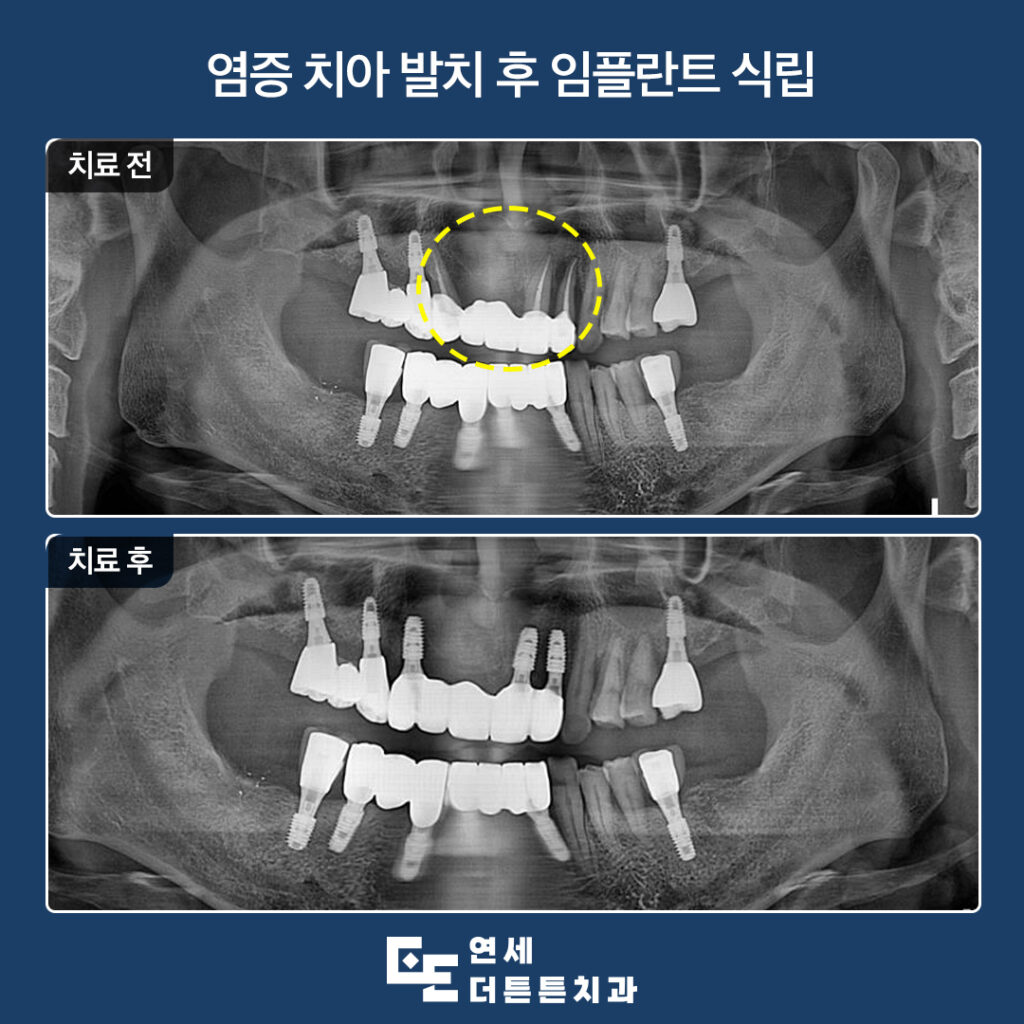

오늘은 염증이 심한 앞니 브릿지를 제거하고

수락산역치과 앞니임플란트를 진행하신 환자분을

소개해 드리도록 하겠습니다.

겉으로 보기에는 문제가 없는 듯 보였으나

파노라마를 촬영해 보니, 지탱하고 있던 양쪽

지대치 뿌리 쪽 염증으로 인해 잇몸뼈가 거의

남아 있지 않을 만큼 녹아 있었고

살려 쓰기에는 무리가 있다고 판단되어

발치 후 임플란트 식립 계획을 수립하였습니다.

최종 보철물까지 완성한 모습입니다.